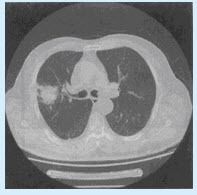

男,62岁。胸闷、体重下降2个月。CT检查如图。

(单选题)最可能的CT诊断为()

A:周围型肺癌

B:炎性假瘤

C:结核

D:错构瘤

E:增殖性炎症

第2题,共2个问题

(单选题)进一步明确诊断应首选以下哪项检查()

A:高分辨率CT检查

B:CTA

C:C、MR

D:USG

E:CT增强检查